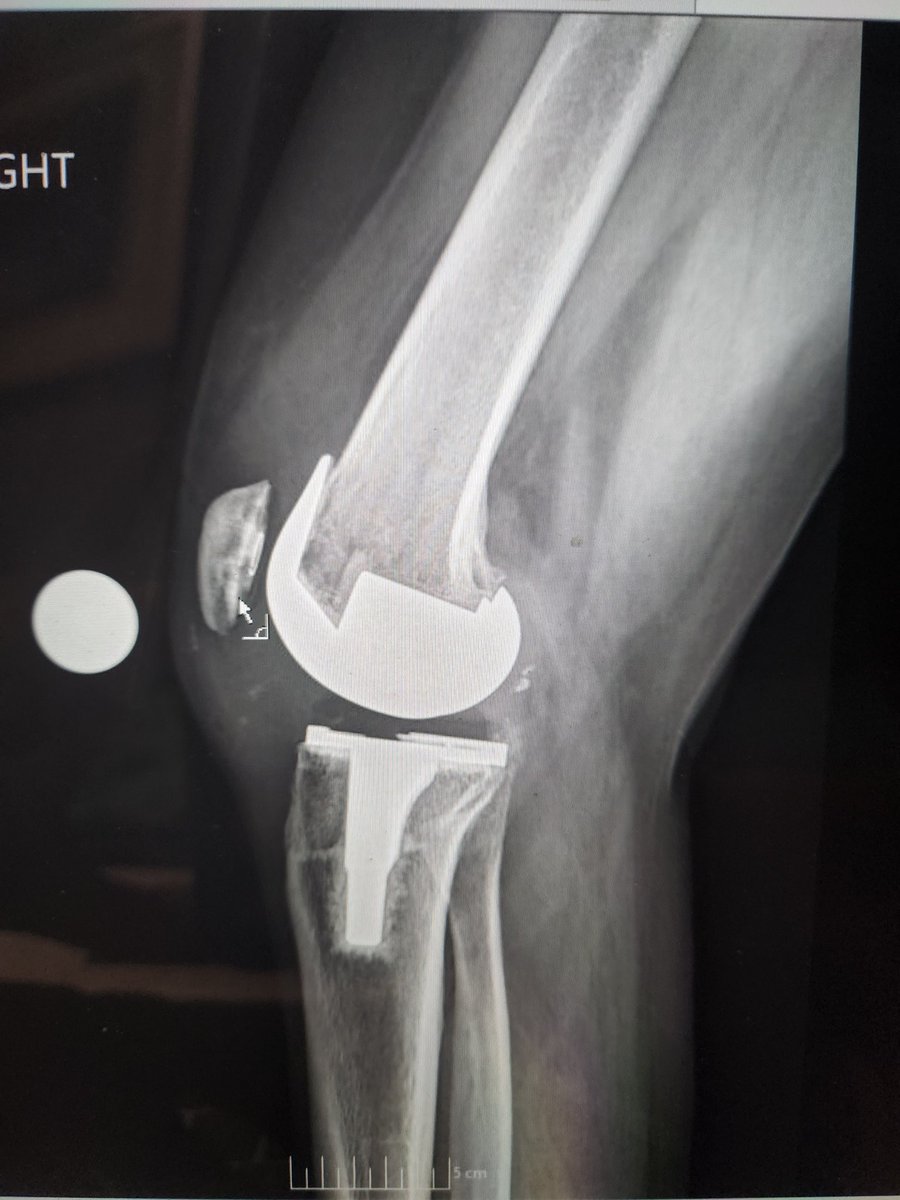

@CenterRotation @djschuett @kate_wynne @Dr_Stambough @BrianChalmersMD @jaimelbellamyDO @ashtongoldmanmd @EdinburghKnee @generalorthomd @orthosmash69 @txsportsdoc I mean I thought part of the joint surgeon uniform was total knee socks 🤷🏼♂️ Am I doing it wrong?